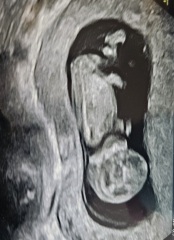

I’ll wait to hear if anyone wants to see a picture. I don’t want to flood this thread with difficult things people need to scroll past xxx Love to you all.

I’d love to see a pic ☺️